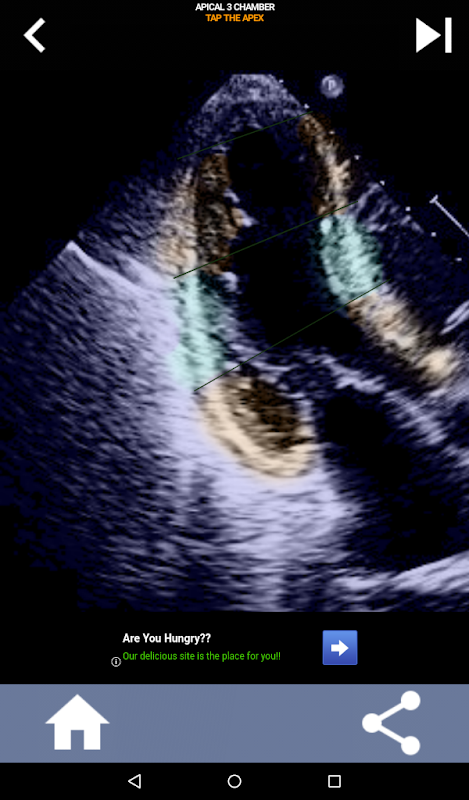

Phương pháp trực quan dựa trên câu hỏi để tìm hiểu các phân đoạn tim AHA: Siêu âm tim

Việc hiểu các phân đoạn tim của AHA (Hiệp hội Tim mạch Hoa Kỳ) là vô cùng quan trọng đối với kỹ thuật viên siêu âm tim để giao tiếp hiệu quả với bác sĩ tim mạch viết báo cáo. Bằng cách biết các vùng giải phẫu cụ thể và các phân đoạn tương ứng của chúng, kỹ thuật viên siêu âm có thể mô tả và truyền đạt chính xác bất kỳ sự bất thường hoặc phát hiện nào, đảm bảo giao tiếp rõ ràng và ngắn gọn giữa cả hai chuyên gia.

Ứng dụng này sẽ kiểm tra kiến thức của bạn bằng cách sử dụng hình ảnh tiếng vang thực tế, mà tôi thường thấy là phương pháp giảng dạy tốt nhất.